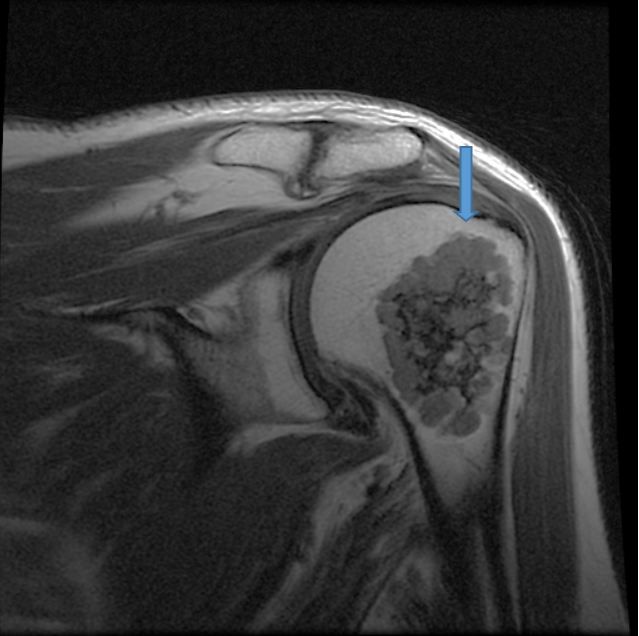

Based on the appearance of the lytic lesion in this patient, the orthopedic physician’s clinical judgement was that it was benign. Consequently, he repeated the radiographs (Figure 2). Even though the chance of malignancy (low-grade chondrosarcoma) is approximately 1%, this patient had noncontrast CT (Figure 3) and MRI (Figure 4) scans.

Figure 4. Noncontrast multisequence mutiplanar magnetic resonance (MR) imaging demonstrates a well-circumscribed lobulated lesion within the metaphysis of the proximal humerus demonstrating heterogeneous diminished signal on T1-weighted images and heterogeneous bright signal on T2-weighted images characteristic of chondroid matrix. It measures 5.1 cm length x 3.9 cm in width x 2.9 cm in AP dimension. The adjacent cortical bone is intact with no endosteal scalloping. There is no soft tissue component. Impression: benign-appearing enchondroma.